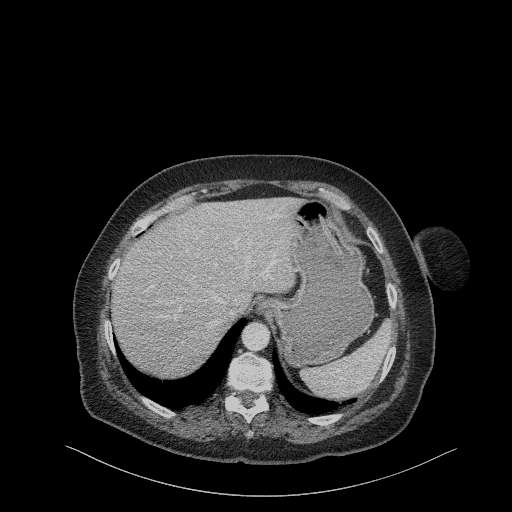

Image Grid

4Γ—3 grid: Rows show different image types (Original NATIVE, Reconstructed NATIVE, Original VENOUS, Generated VENOUS), Columns show windowing techniques (No Window, Lung Window, Mediastinum Window)

Original NATIVE CT scan (input)

Full window (WL 1023.5, WW 4095 β†’ Low βˆ’1024, High +3071)

Generated VENOUS CT scan (A→B translation)